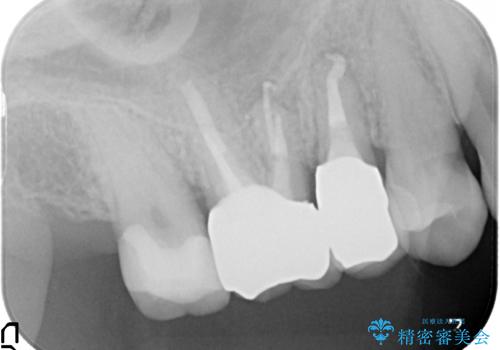

歯周外科・根管治療による長期予後を期待する奥歯の治療

- 歯周外科による歯肉・歯の相対的な位置関係の改善

→治癒待ちの間に再根管治療、ファイバーコアの築造

→セラミッククラウンの製作

詰め物の種類:e.max press In

かぶせ物の種類:PFZ Standard